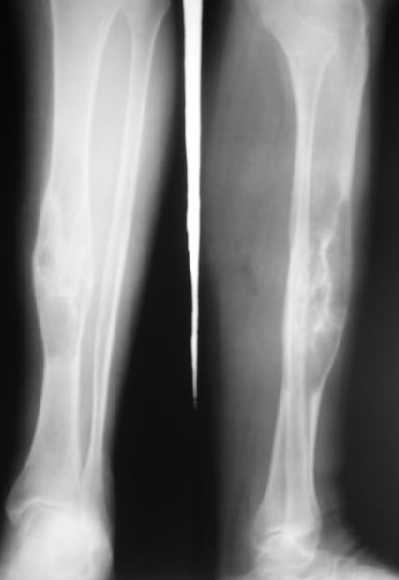

The diagnosis radiologically and post resection specimen coincides with typical osteofibrous dysplasia more than GCT.

I have some doubt about the diagnosis. Are you sure that this is a benign lesion? Has she pain? The age of the patient, specimen and X-rays don't exclude other more aggressive lesions. Do you have a preoperatory CT or NMR?

Yesterday our pathologist presented a preliminary conclusion - lytic GCT. Will pass specimens to colleagues from other facilities.

I spent my early orthopaedic surgical experience at an Italian bone tumor center. I have seen many GCTs of the bone, but none is similar to that you presented. I hope that this is a my error, but

it, in my opinion, appears aggressive and strange in diaphyseal localization. It seems in some aspects similar to a teleangectatic osteosarcoma, a variant of osteosarcoma (characteristic gross appearance of telangiectatic osteosarcoma is a multi-cystic "bag of blood". Microscopically, telangiectatic osteosarcoma has large blood filled spaces and thin septation. Within the septa there is scanty osteoid production by the pleomorphic malignant cells. Giant cells are not rare)

Пока наш морфолог подтверждает гигантоклеточную опухоль, литическую форму. Препараты передали еще и в другие учреждения, пока информации оттуда нет.